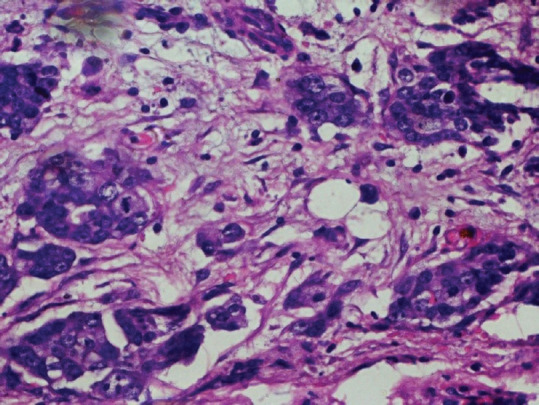

Gallbladder carcinoma (GBC) is the most common malignant tumor of the biliary system and presents with frequent locoregional lymphadenopathy and distant metastasis. Gallbladder tuberculosis (GT) is rare abdominal tuberculosis (TB). GBC and GT mimic each other. The clinical examinations and radiographic investigations sometimes fail to exhibit the difference between these two which are confirmed only after postoperative histopathological assessment. Herein, we report a patient of GBC with coexistent GT with pleural metastasis and pleural effusion. We emphasize the importance of differential diagnosis of the two conditions, with similar signs and symptoms. The pleura is an extremely rare site of spread of GBC as seen in our patient.